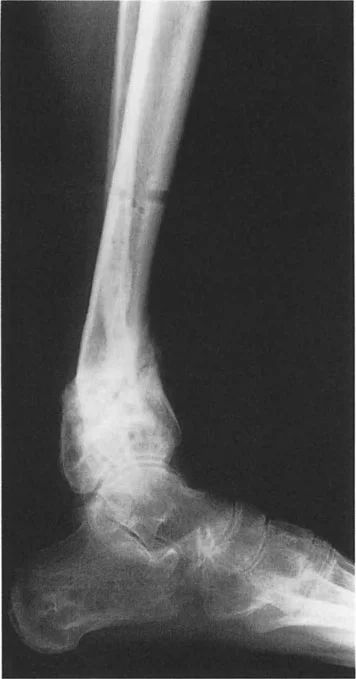

أمراض المستوى السهمي (الركبة الخلفية/الانحناء الأمامي - Recurvatum/Procurvatum):

يحدث التحميل غير الطبيعي أيضًا نتيجة للتضحية بحركة المفصل في المستوى السهمي. لننظر إلى تشوه الركبة الخلفية (recurvatum) في الجزء البعيد من عظم الساق (القمة الخلفية). لتسطيح القدم، يجب على المريض التعويض عن طريق ثني الكاحل بشدة (plantarflexion). يؤدي هذا الانثناء التعويضي إلى كشف الجزء الأمامي من قبة عظم الكاحل.

تظهر الأبحاث أن ما لا يقل عن 5 درجات من الركبة الخلفية مع الانثناء التعويضي يقلل من منطقة التلامس بين عظم الساق وعظم الكاحل بنسبة مذهلة تصل إلى 30%. وفقًا للفيزياء الأساسية (الضغط = القوة / المساحة)، فإن تقليل منطقة تحمل الوزن بنسبة 30% مع الحفاظ على نفس حمل وزن الجسم يزيد بشكل كبير من الضغط لكل وحدة مساحة على الغضروف المتبقي. يؤدي هذا الحمل المركز على الجزء الأمامي من مفصل الكاحل حتمًا إلى تآكل الغضروف الميكانيكي والتهاب مفصل الكاحل المبكر.